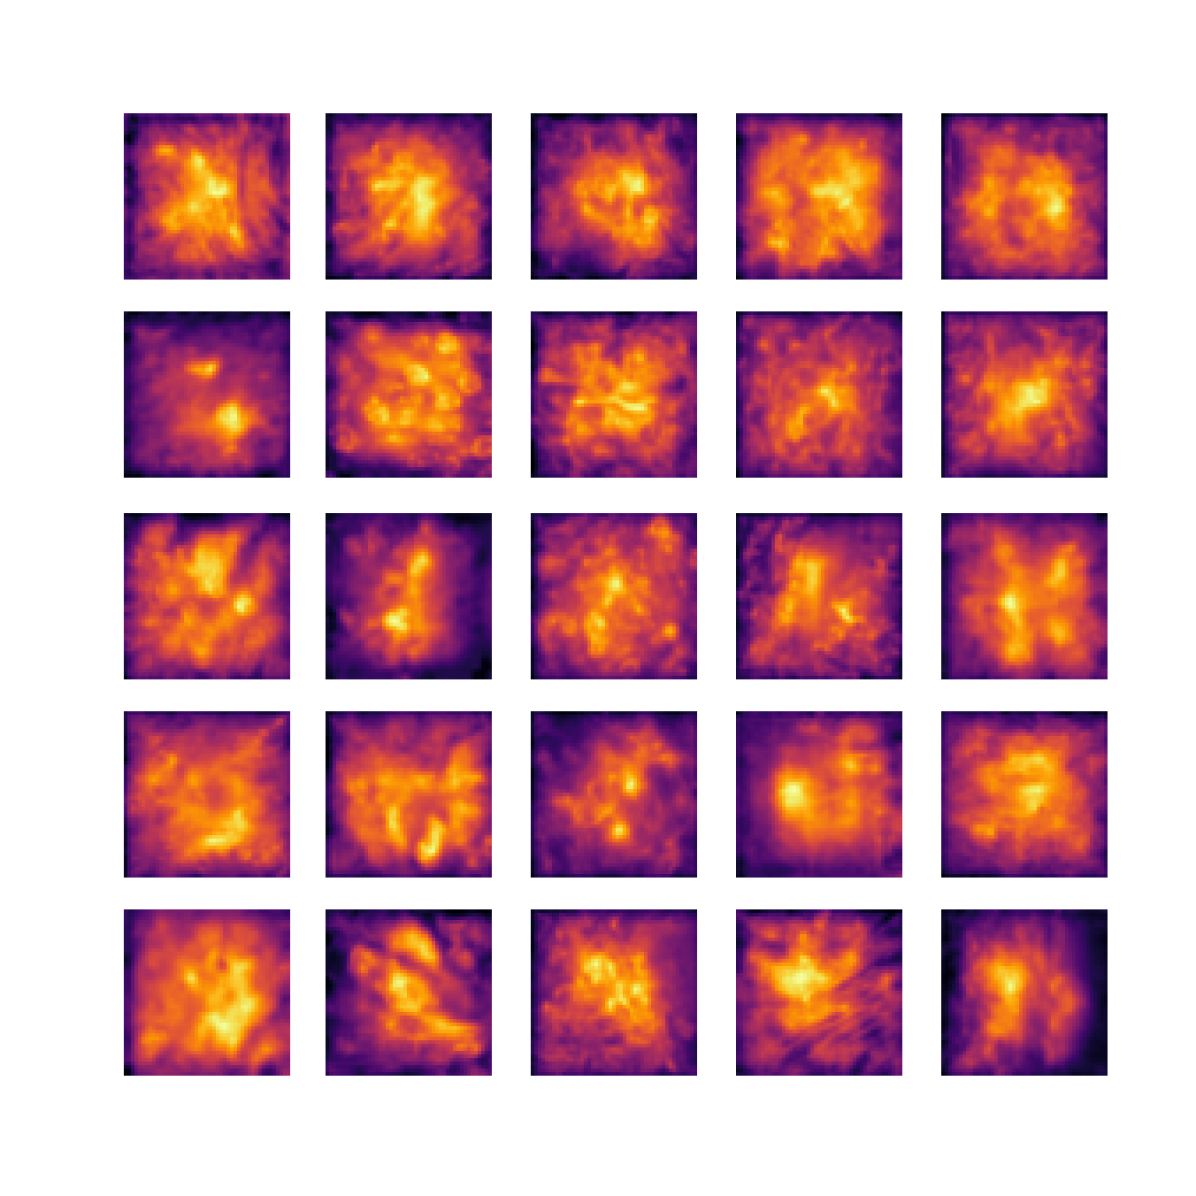

We also analyse the activation maps for each model using GradCAM as described in section S3. This offers more insight into the areas of the image which are contributing most heavily to the models’ representations. In Figure 4(b) we present some representative examples, however, a larger selection which was chosen at random is presented in Figures S10 to S25. The larger selection makes it easier to see the emergent patterns, including that privileged Siamese models tend to mainly identify features which are strongly present in both inputs, while unprivileged Siamese models tend to learn more diffuse features that are not specific to one cell phenotype or image region. TriDeNT ♆ incorporates both sets of features, learning both features specific to the privileged data and more the general features associated with unprivileged Siamese networks.

We can see in Figure 4(b) panel A that for ERG, the privileged Siamese model focuses almost exclusively on any nuclei which could be endothelial cells. As there are very few endothelial cells in the dataset, it could be an effective strategy to identify anything that could potentially be an endothelial cell to minimise the difference between the representations of the H&E model and the IF mask model. In the corresponding unprivileged Siamese image, we see that the model identifies some of these nuclei, albeit less strongly, but also focuses heavily on the other tissue and even the background, while strongly fixating on two spots of debris in the center of the image. This model has less ‘incentive’ to learn the weak features related to endothelial cells as these occur rarely and are not easy to detect, while more generic strong features such as the presence of connective tissue and the prevalence of background are more common and predictable from augmented images. We see that TriDeNT ♆ combines these two feature sets, strongly identifying nuclei while also identifying the connective tissue.

In panel C we see a similar pattern, with the privileged Siamese model fixating solely on the nuclei, while the TriDeNT ♆ model takes a more balanced approach. The unprivileged Siamese model appears to focus on a single cluster of nuclei while neglecting others, and similarly identifies an area of fibroblasts with its distinctive pattern but does not others.

In contrast to panels A and C which represent models with poor privileged Siamese results, panels B and D represent models whose privileged Siamese results were comparable to both TriDeNT ♆ and even the supervised baseline. It is therefore interesting to note that there are far more similarities between the privileged Siamese and TriDeNT ♆ models in both cases. Particularly in panel B, TriDeNT ♆ and the privileged Siamese model return virtually identical heatmaps, with both strongly identifying epithelial nuclei and neglecting the same areas of connective tissue. The unprivileged model in this case appears to focus solely on the centre of the image, giving a significantly different heatmap to the other panels.

Panel D again shows the previous pattern, with the privileged Siamese model identifying the features strongly present in the privileged data – fibroblasts – while neglecting the nuclei present. TriDeNT ♆ also strongly identifies the connective tissue, but, unlike the privileged Siamese model, does not completely neglect the nuclei. The unprivileged Siamese model primarily identifies background, and does not appear to identify the nuclei in this example.